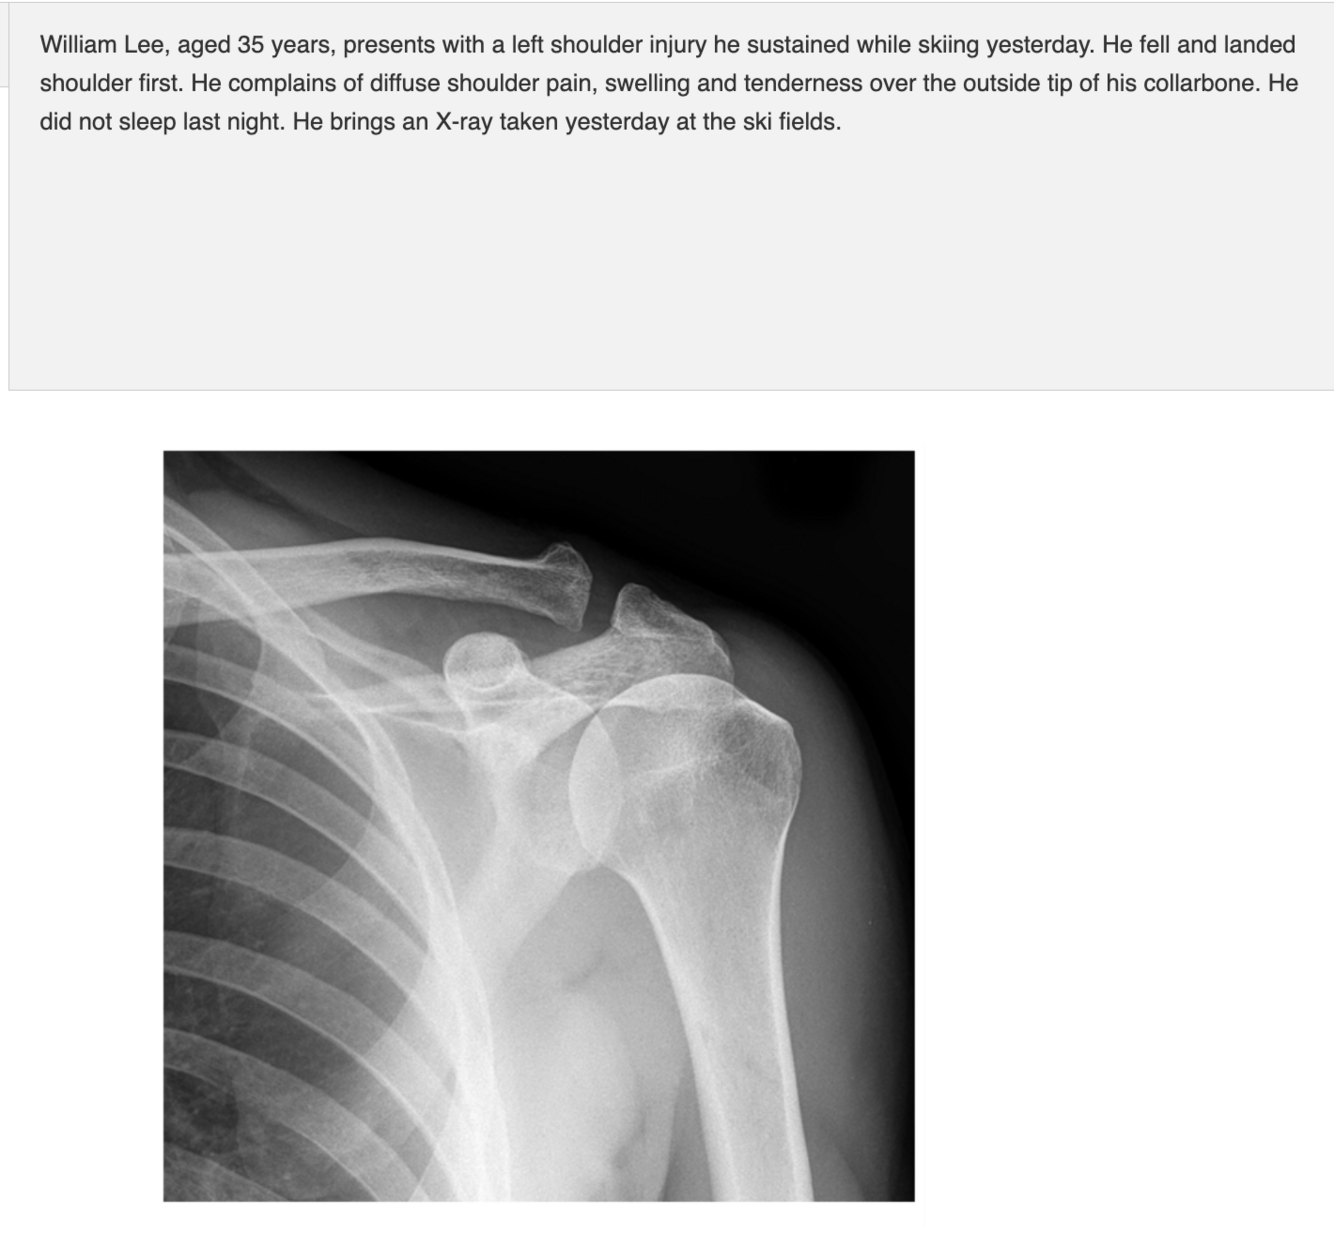

Injury + Management

AC Joint separation / sprain

Most managed conservatively

- 48 hours immobilisation with sling, rice